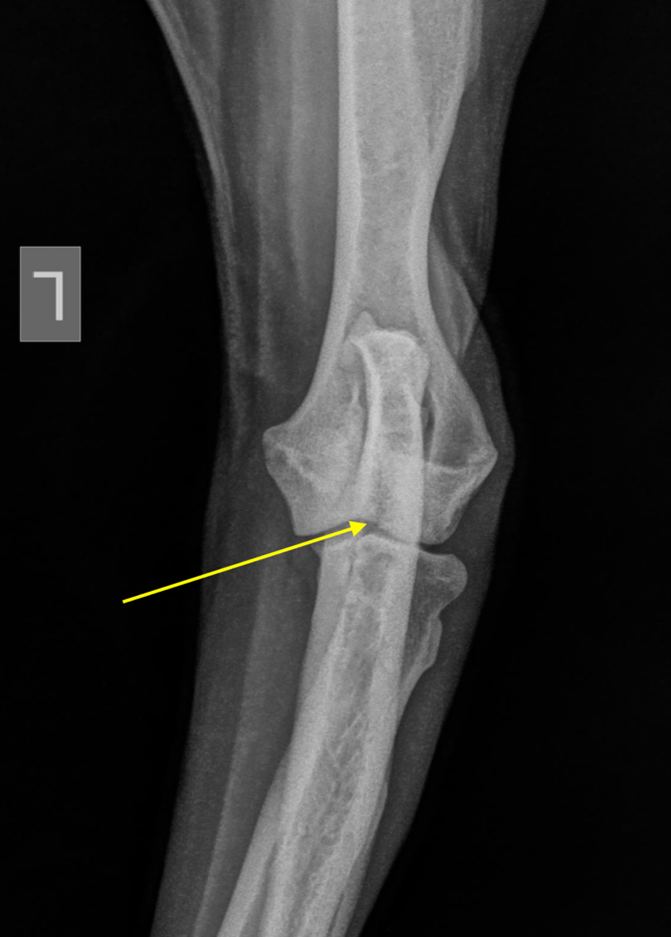

Fig 1. Op deze radiografie is er toch een fissuur lijn zichtbaar intercondylair

Om een duidelijker beeld te krijgen over deze afwijking en omdat de radiografie slechts een discrete fissuur toont die niet overeenstemt met de actuele klinische klacht werd een CT-scan voorgesteld om beide ellebogen meer in detail in beeld te brengen.